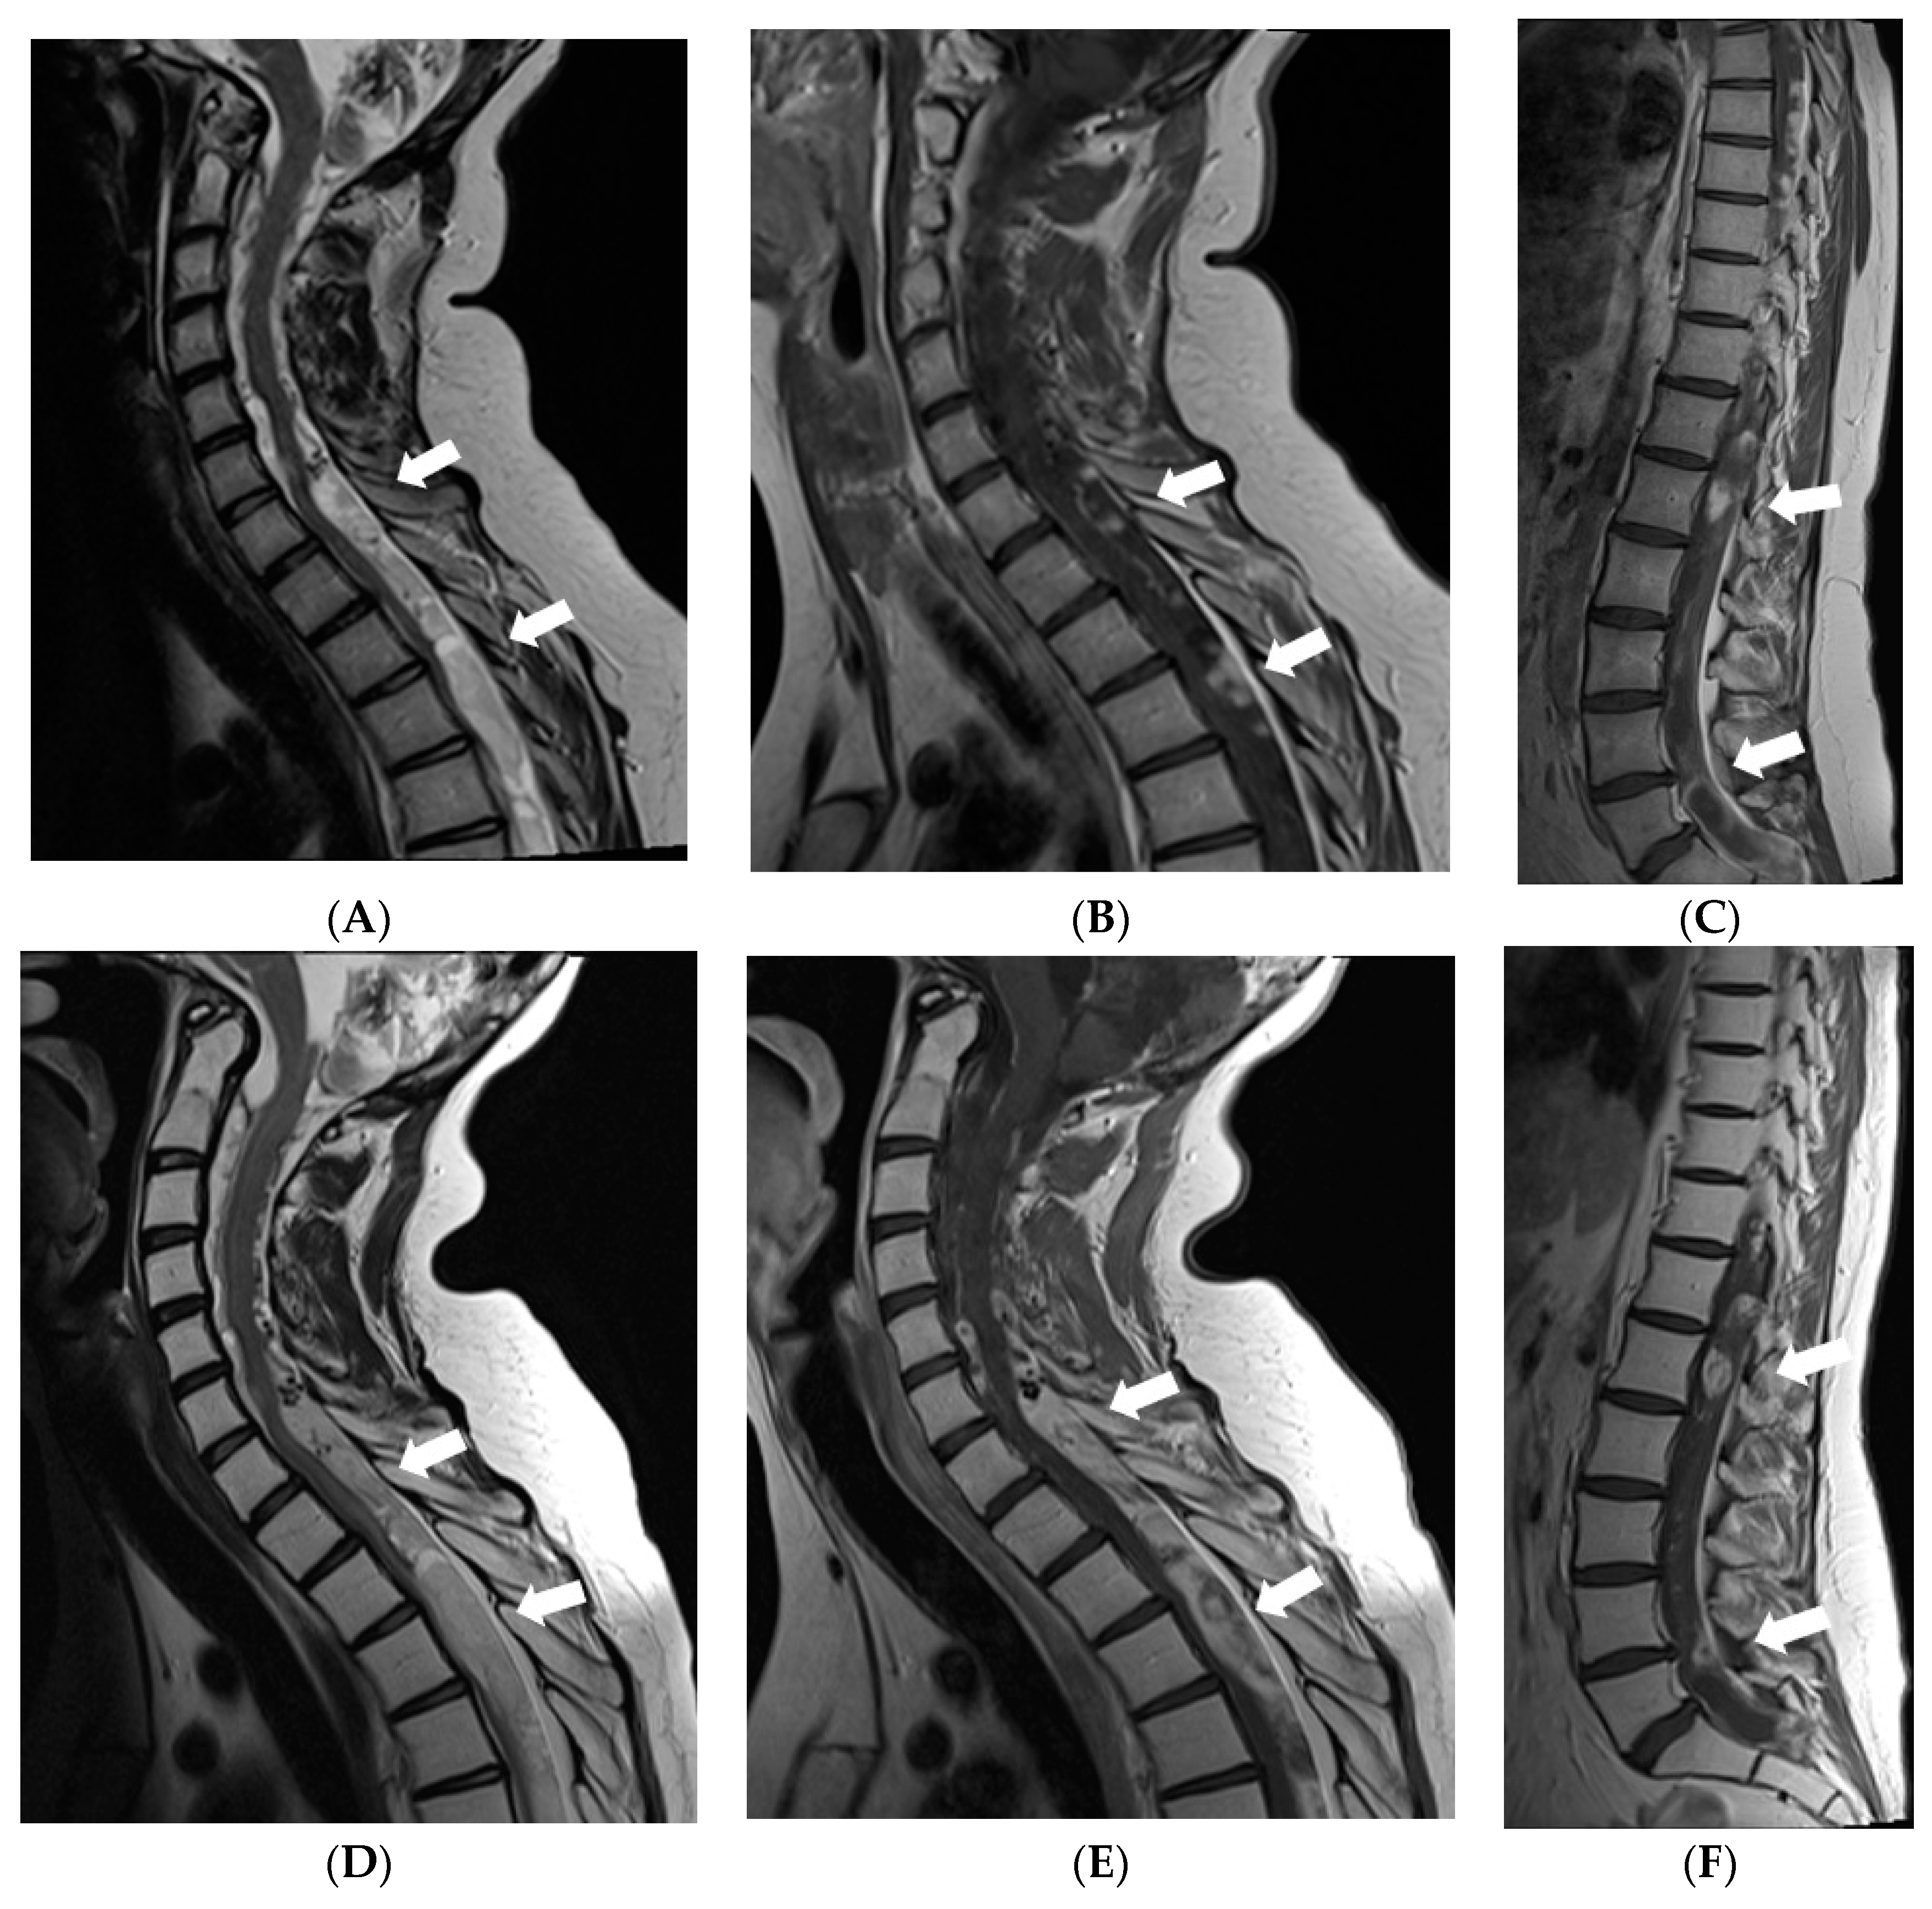

In 2017, follow-up brain MRI scans showed decreased leptomeningeal enhancement and slight decrease in size of cystic lesions in the brain; although, atrophy of the brainstem and cerebellum had progressed. However, spread of the tumour was found in the spinal canal through all its length manifested by diffuse meningeal enhancement and multiple cystic intra- and extradural lesions causing compression of the spinal cord. The girl received radiotherapy to the whole spinal cord; however, masses in the spinal canal progressed (Figure 5). In 2018, right-sided facial reconstructive surgery with medial cantopexy was performed.

Figure 5.

MRI of the spinal cord 6 years after the onset of symptoms: (A,D) Sagittal T2W, (B,E) T1W postcontrast images of the cervical and the upper thoracic spine, (C,F) postcontrast images of the middle/lower thoracic and the lumbar spine. In May 2017, (A–C) multiple confluent cystic extramedullary masses were found in the spinal canal through all its length, compressing the spinal cord at the level from C6 to T9 vertebrae. There was some nodular contrast-enhancement in the tumourous masses and diffuse meningeal enhancement. After radiotherapy in December 2017 follow-up MRI (D–F) demonstrated enlargement of the extramedullary masses in the lower cervical-upper thoracic spine with more vivid and diffuse enhancement, also, more vivid diffuse meningeal enhancement.